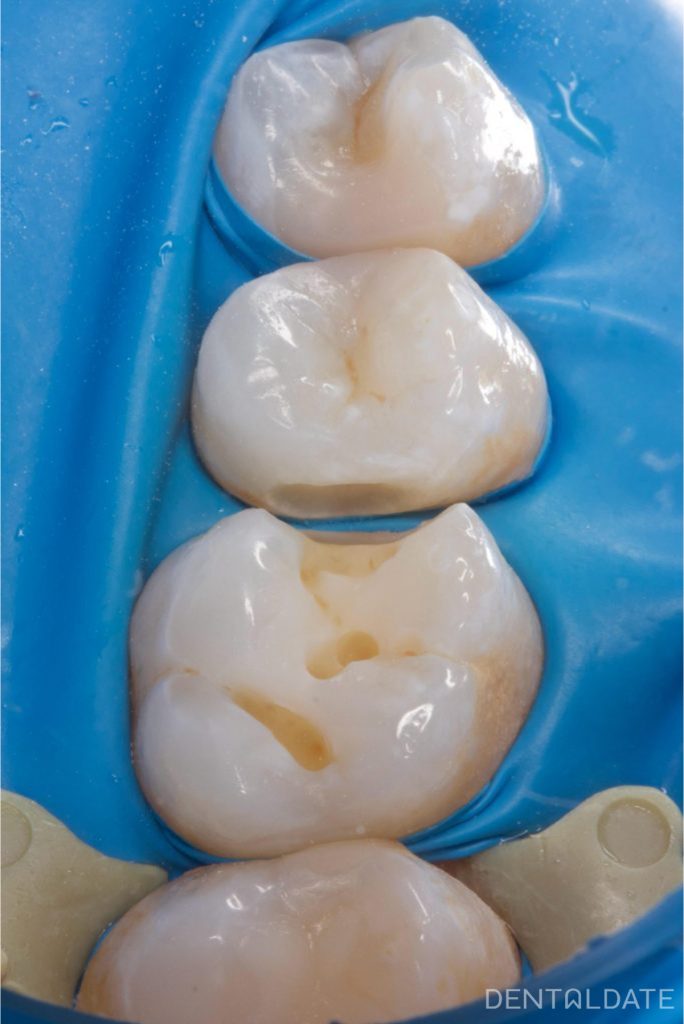

During treatment, decay was also discovered on a neighbouring tooth.

Once all infected surfaces have been cleaned, the teeth are prepared for restoration.